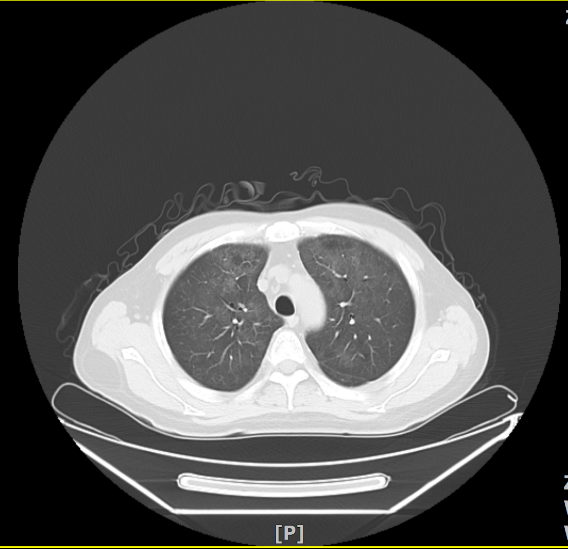

2020年10月27日因“淋巴瘤化疗后发热5天”来我院治疗。入院时血常规正常,CRP51.75mg/L,PCT阴性,血气未见明显异常,血清(1-3)-β-D-萄聚糖阳性(G试验)549.14pg/ml(≥100pg/ml阳性),GM试验阴性,LDH 537.3U/L、CMV和EB病毒定量阴性;胸片示肺间质改变明显,胸部CT示两肺弥漫磨玻璃样模糊影,考虑PCP可能大。

PCP影像学随着病程进展呈现动态变化,疾病不同时期表现可明显不同,典型表现为双肺弥漫性或局限性磨玻璃样影像,星云雾状、树枝挂霜样改变,呈非对称性、非均匀性随机分布;慢性或复发病例可引起间质结构和小叶间隔的增厚。